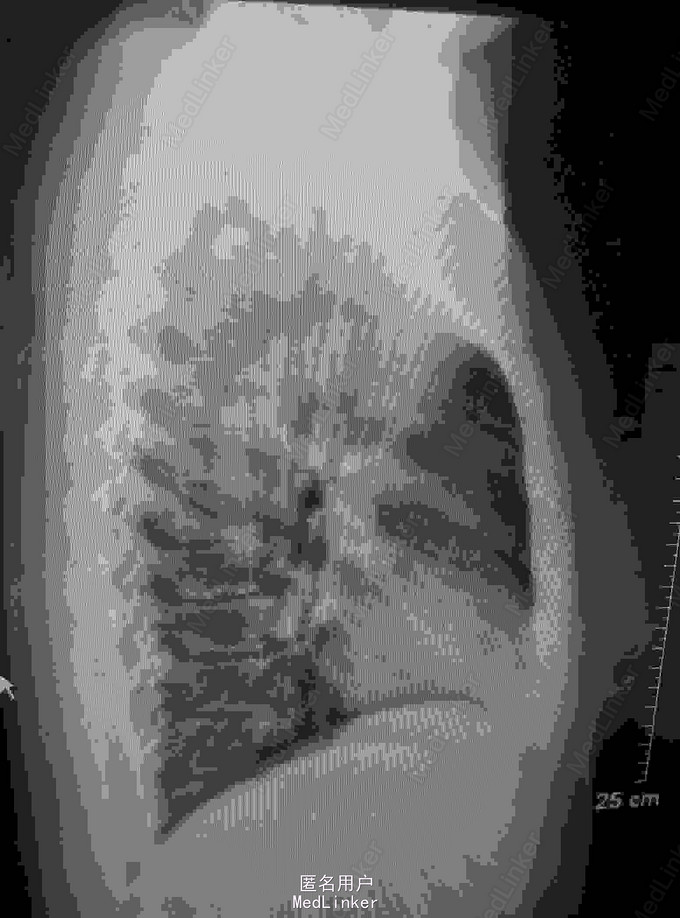

患者,女,51岁,右乳癌术后10月余,出现双肺转移1周 患者原发肿物位于右乳12点距离乳头2cm,大小约1.9*1.6cm,于2014-9-25行右乳癌改良根治术+前哨淋巴结活检术,术后病理示:RIDC,III级,ER(-)、PR(-)、HER-2(-)、Ki-67(+,70%),术后行EC*4-T*4化疗.

2015-08-19:我院胸片和CT示双肺多发结界影考虑转移瘤

诊断:右乳癌术后伴双肺转移 治疗:入院行骨扫描检查未发现转移,行GX方案姑息性辅助化疗